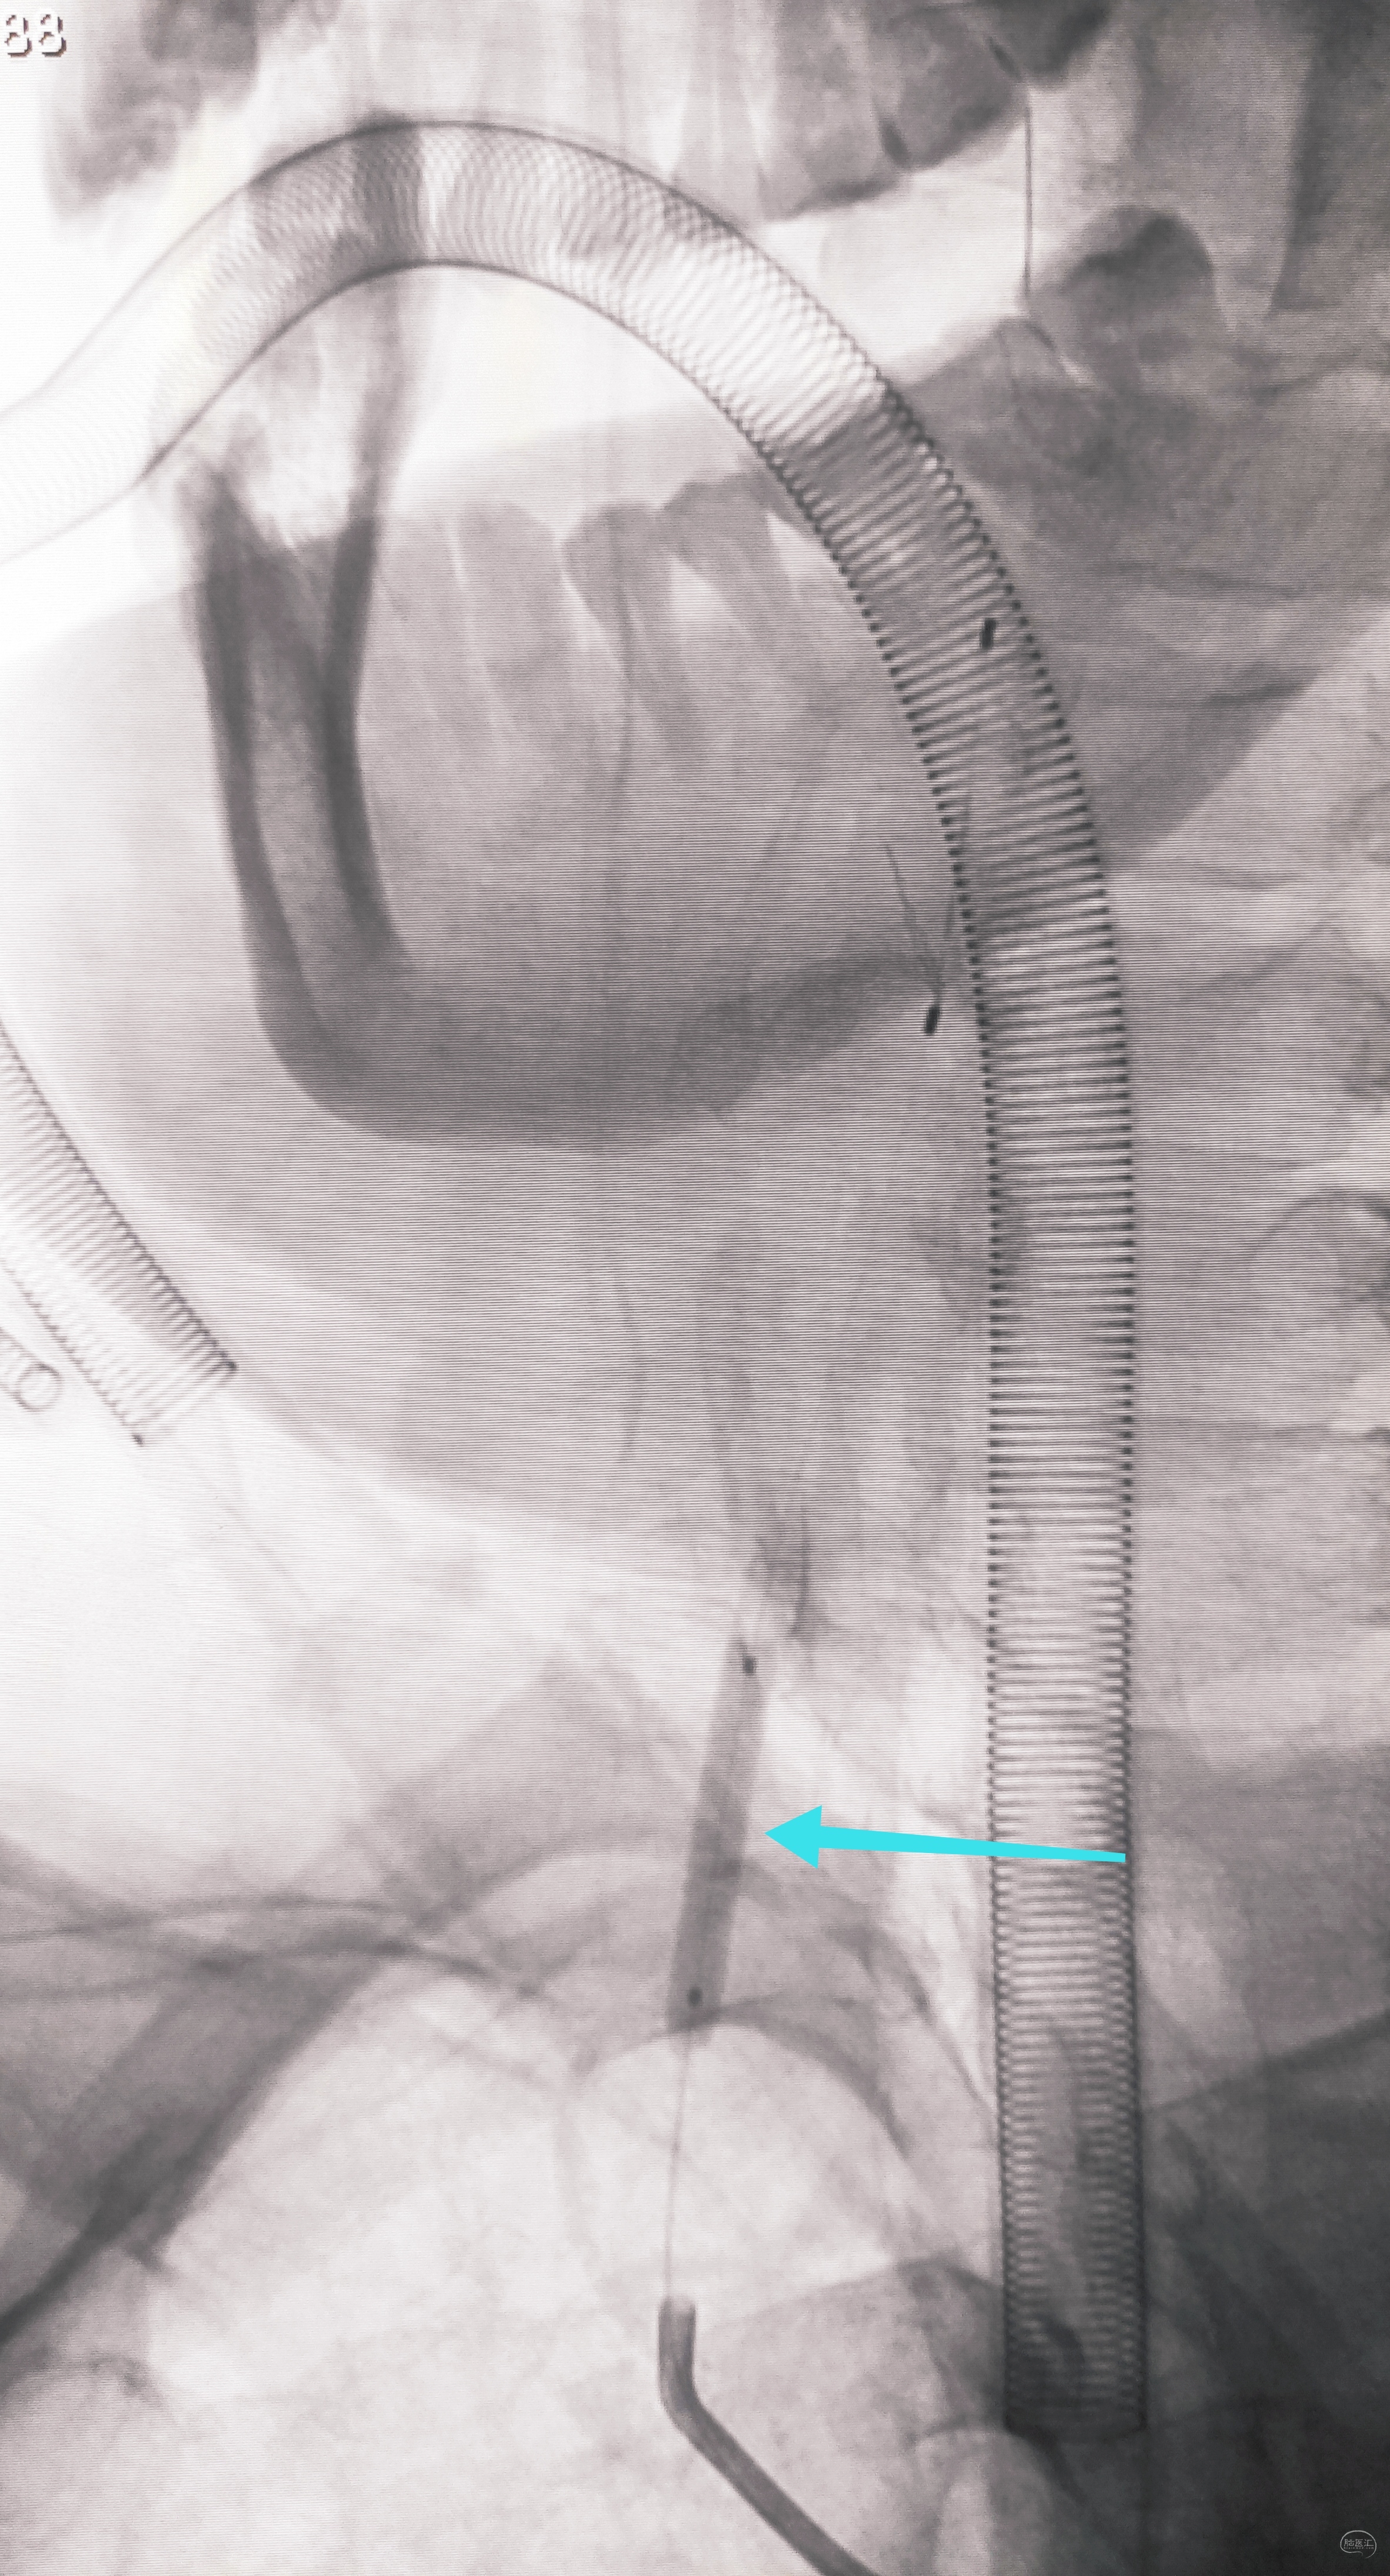

泥鳅两段露头,8F导引导管沿泥鳅攀爬,一把干到左侧肱动脉为止

6F导引导管造影确认支架置入部位

支架导引导管内先通过,再回撤技术,顺利释放雅培9×29球扩支架